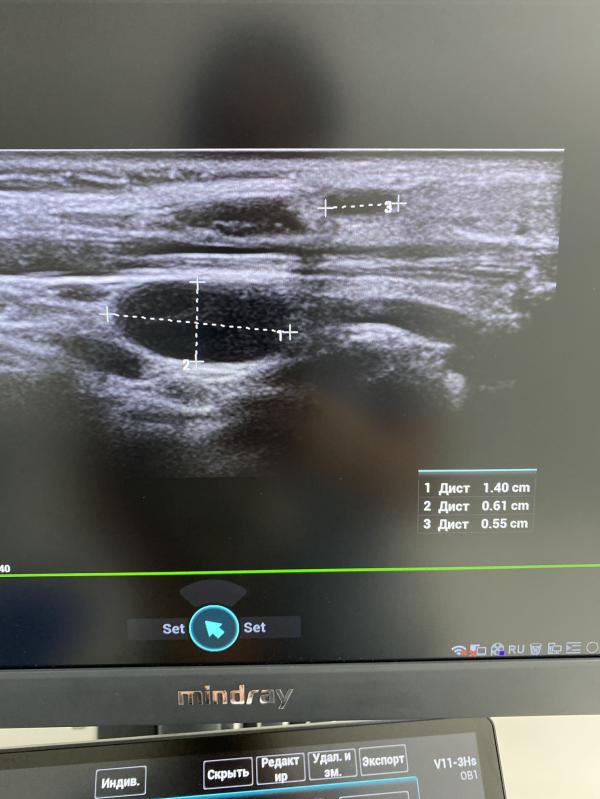

Эпидемический паротит: как распознать и что делать? УЗИ для выявления абсцесса лимфоузлов и воспаления яичек

Узи исследование проводится для своевременного выявления абсцесса лимфоузлов.

А так же исключить воспаление яичков у мальчиков.